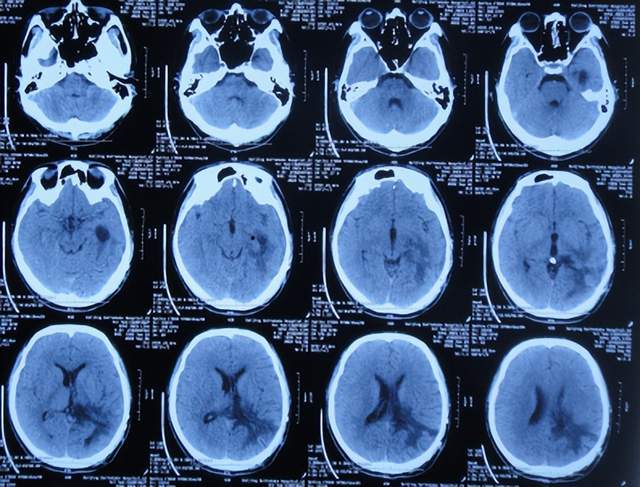

继续抗感染治疗1周的时间,仍精神差,食欲差,间断发热,期间3次查头颅影像(2021年1月29日头颅核磁增强(图-10)、2021年1月31日头颅CT(图-11)、2021年2月3日头颅核磁增强(图-12)均示颞角逐渐有扩张,有感染。

图-10:2021年1月29日头颅核磁增强

图-11:2021年1月31日头颅CT

图-12:2021年2月3日头颅核磁增强

2021年2月5日(脑膜瘤切除术后颅内感染3周)住入李小勇脑脊液科,入院时:精神差,食欲差,体温高(图-13);查头颅CT示脑瘤术后状态(图-14);(外院)2021年2月3日头颅核磁示有脑脓肿(图-12)。

图-13:2021年2月5日入院时

图-14:2021年2月5日头颅CT

入院后3天即2021年2月8日,左颞角脑室腹壁外引流术(图-15)。

图-15:2021年2月8日头颅CT

左颞角脑室腹壁外引流术后8天即2021年2月16日,查头颅CT示颞角缩小(图-16)。

图-16:2021年2月16日头颅CT

左颞角脑室腹壁外引流术后21天即2021年3月1日,查头颅CT示颞角仍有扩张(图-17)。

图-17:2021年3月1日头颅CT

左颞角脑室腹壁外引流术后23天即2021年3月3日,头颅CT增强和核磁增强示有脑脓肿(图-18、图-19)。

图-18:2021年3月3日头颅CT增强

图-19:2021年3月3日头颅核磁增强